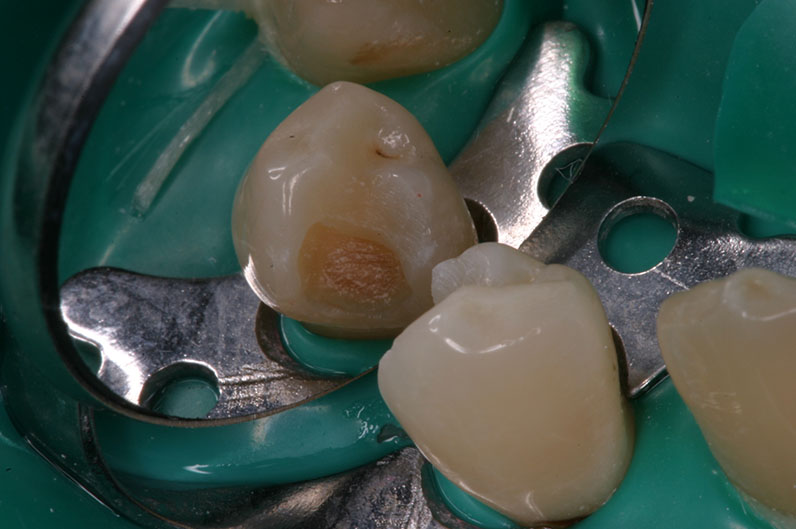

Преди екскавиране